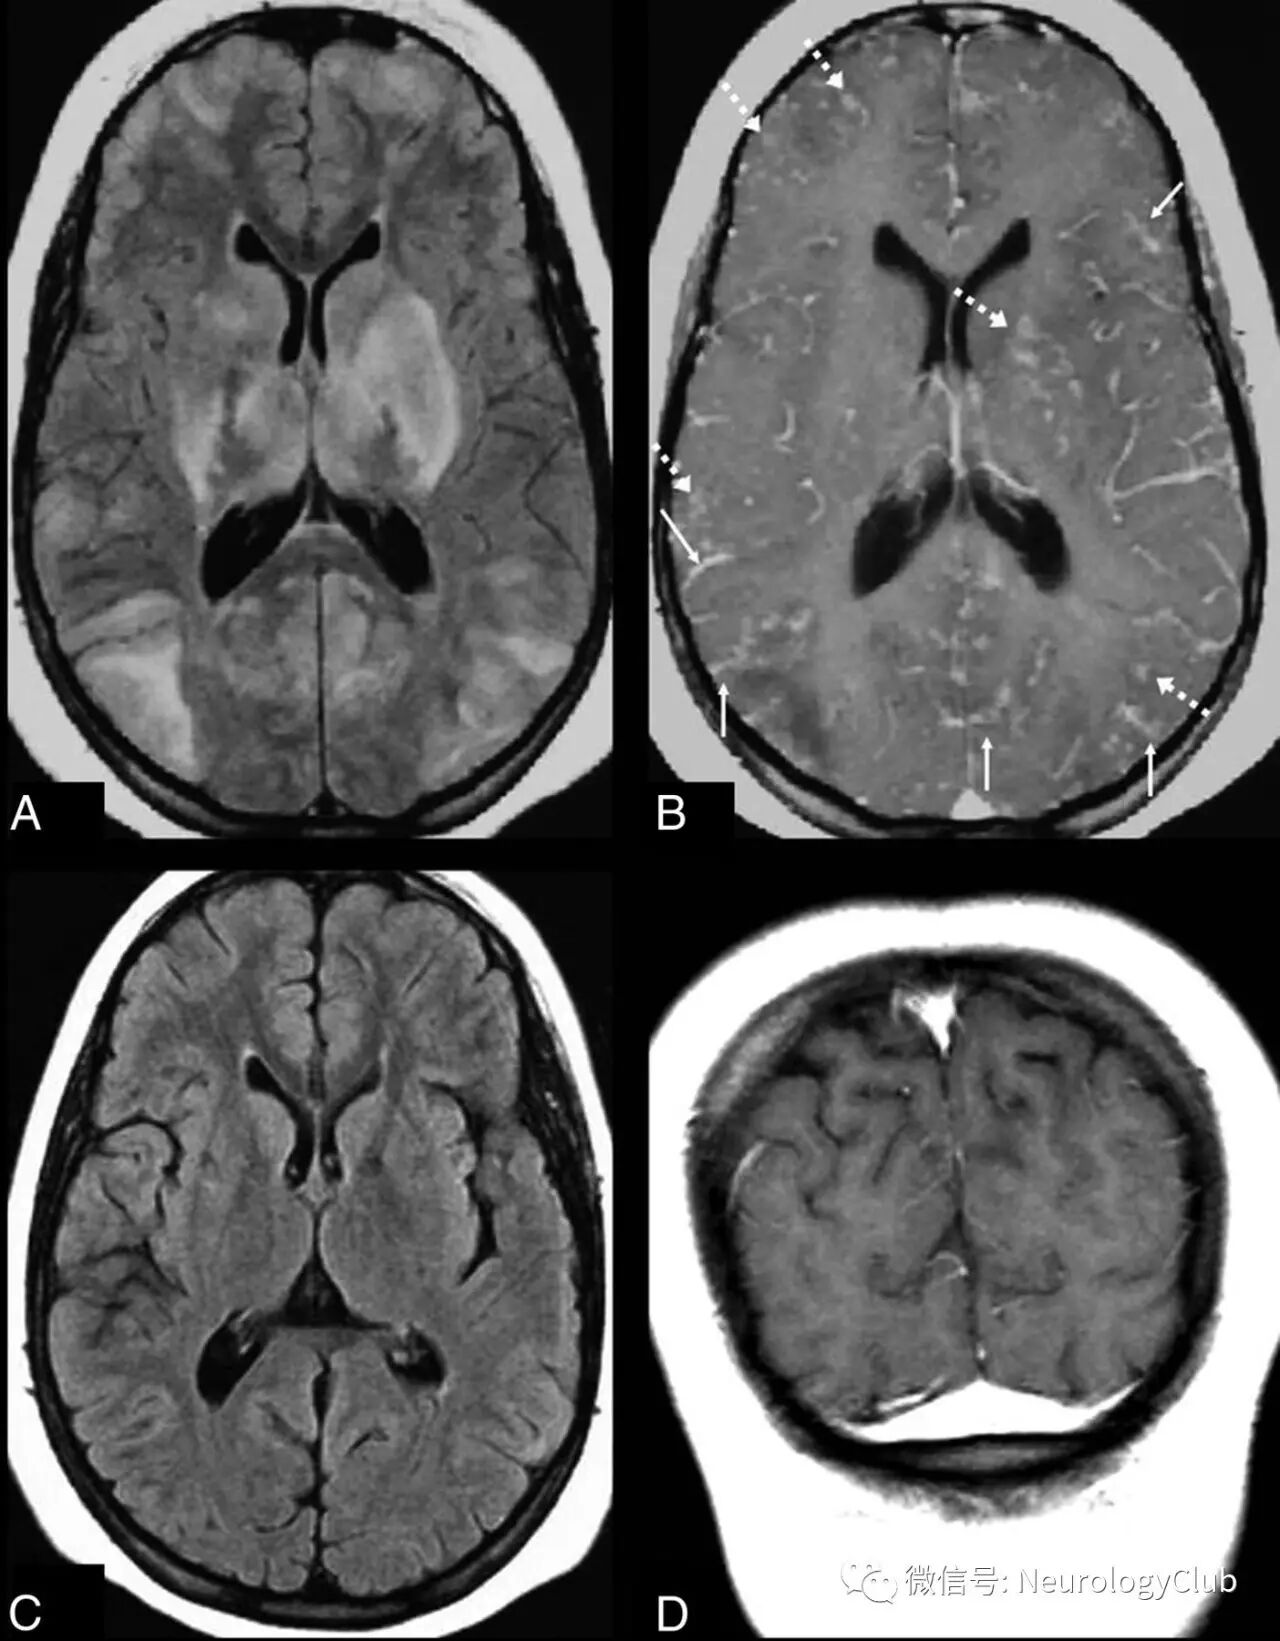

颅脑影像学有助于诊断PRES以及鉴别诊断。血管源性水肿可以通过CT来发现,但颅脑MRI更敏感。由于缺乏诊断金标准,无法评估MRI的特异性。颅脑MRI典型表现为双侧顶枕叶为主的血管源性水肿,呈T1低信号,T2/FLAIR高信号,DWI等或低信号,ADC高信号。通常累及皮质下白质,较少累及皮质。水肿几乎累及双侧,不完全对称。

(图2:典型的黑水像PRES影像学表现)

影像学表现可分为四型:顶枕型,全脑分水岭型,额上回型和中央变异型。影像学分型和水肿严重程度都不与临床表现分型和严重程度相关。额叶和颞叶受累者约占75%。累及基底节和脑干者有1/3,累及小脑者约占半数。这些部位的水肿一般是伴随着顶枕部位的受累。病变不累及顶枕区域者少见。仅累及单侧大脑和孤立性脑干与小脑水肿者需要排除其它疾病。